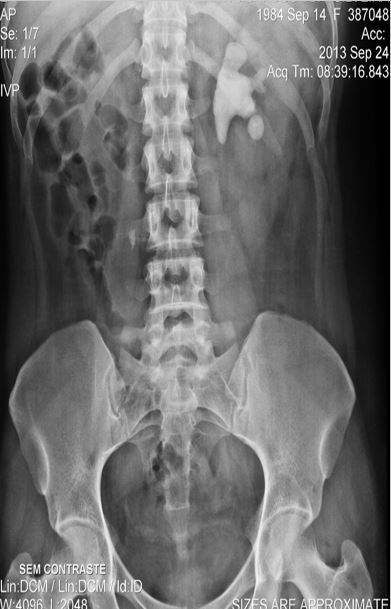

DOR NO HIPOCÔNDRIO D

ACHADOS? DIAGNÓSTICO? QUAL EXAME VC SOLICITARIA PARA CONFIRMAR O DIAGNÓSTICO?

Há duas imagens cálcicas justapostas em projeção do Hipocôndrio D.

Colecistopatia Calculosa

USG do abdome superior ou do Hipocôndrio D ou Urografia Excretora para descartar Litíase na Pelve Renal.

Confirmou Colecistopatia Calculosa.